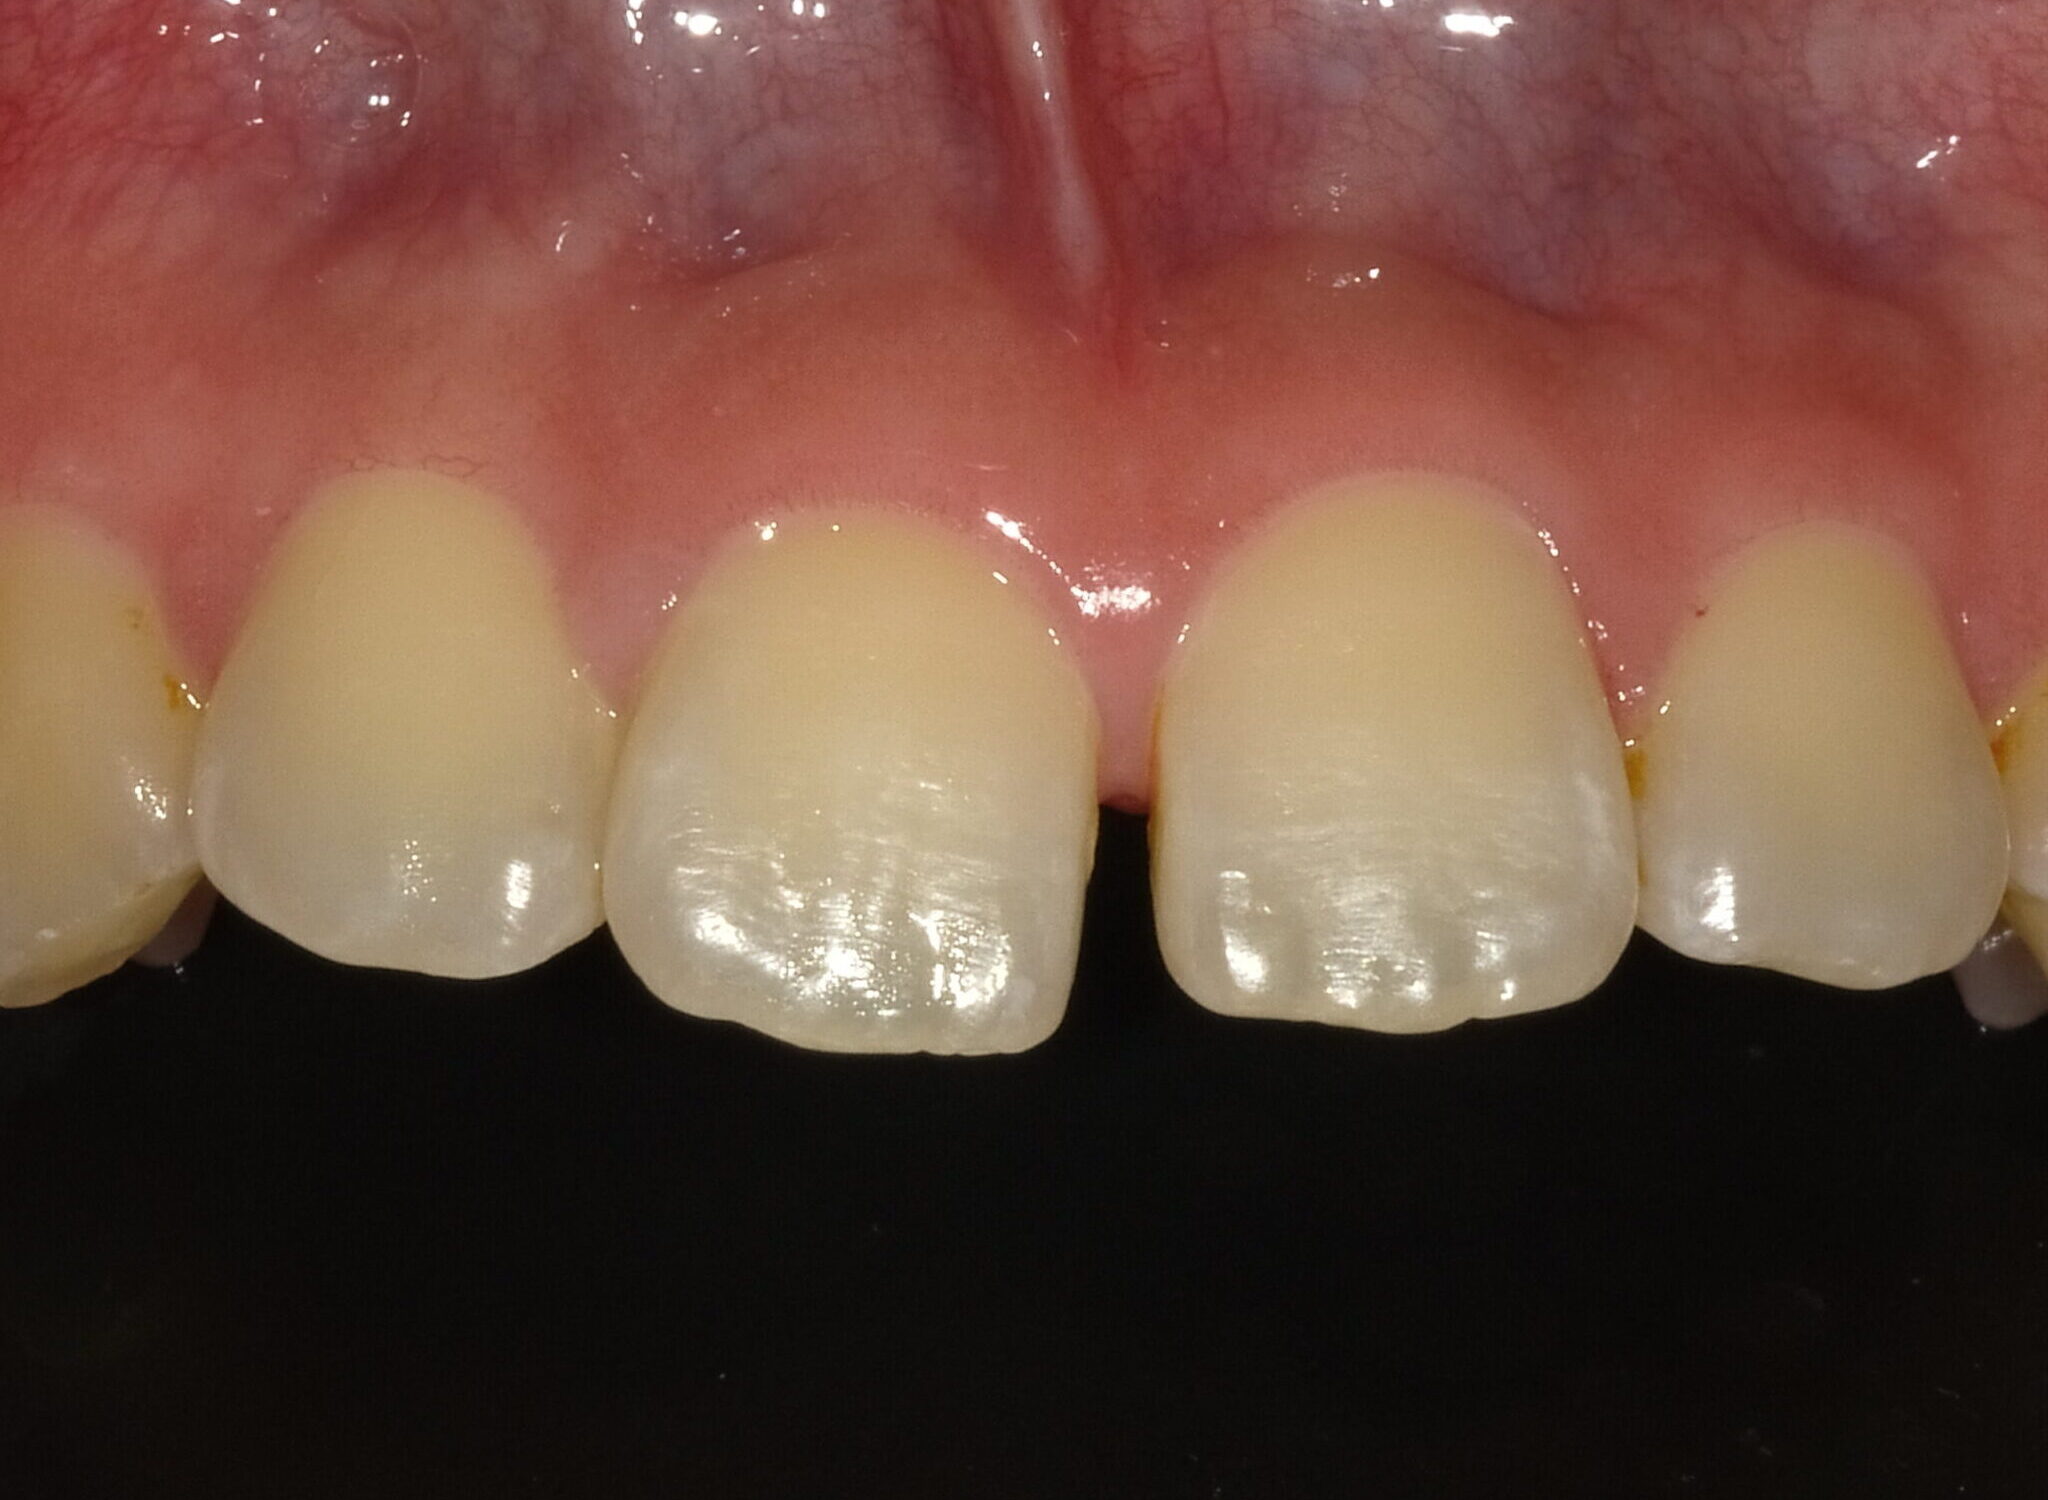

虫歯治療decay

審美歯科esthetic